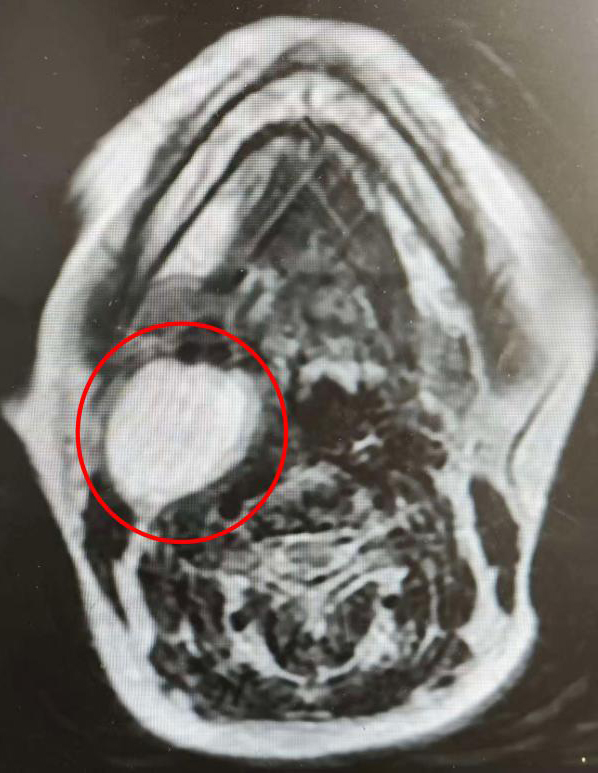

患者黄爷爷(化名)今年91岁。其实,早在十年前,他的右耳后就已出现一个“鸭蛋”大小的包块,因无明显不适而未重视。然而一周前,这个沉寂多年的肿物突然迅速增大,长至成人拳头大小,并伴有明显疼痛。家属紧急将其送至市一医就诊,经穿刺检查,被诊断为“右侧腮腺区肿物”,需手术治疗。

患者超高龄、肿瘤巨大且位置深,紧邻面神经及颈部大血管,手术风险极高。耳鼻咽喉科主任王为高度重视,立即组织科室与麻醉科、老年病科、肾病内科、重症医学科(ICU)等多学科专家进行讨论,全面评估手术风险,精心制定手术方案及围术期管理策略,力求在根治肿瘤的同时,最大限度保障患者安全与术后生活质量。

手术由耳鼻咽喉科副主任彭炜主刀,姚伟主治医师担任助手。术中探查发现,肿瘤与面神经分支粘连紧密,团队在高倍显微镜下精细操作,成功分离并保护面神经各分支,最终将肿瘤连同受累腮腺组织完整切除。手术过程顺利,出血量控制良好。